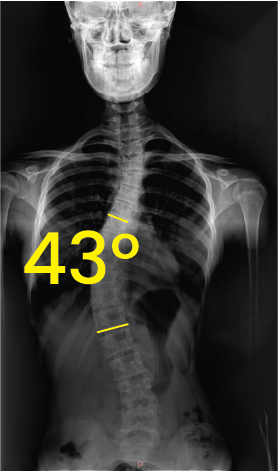

Toraks bölgesinde 43 derece açıyla eğri omurga gösteren röntgen görüntüsü.Göğüs ve omurga röntgeni, omurgada 19 derece eğrilik işaretiyle skolyoz gösteriyor.

Omurga eğriliğini gösteren 55 derece açıyla skolyozlu gövde röntgeni.Göğüs bölgesinde 43 derece eğimli skolyozu gösteren omurga röntgeni görüntüsü.